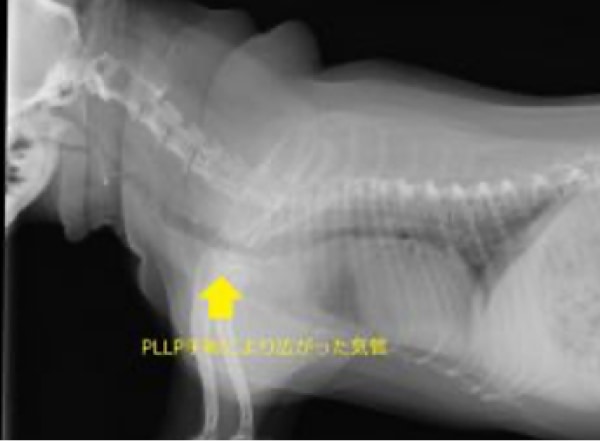

気道の狭さ:短頭種は、鼻や喉などの気道が短く、狭くなっています。これにより、空気の流れがスムーズでなくなり呼吸困難が生じます。具体的には鼻孔狭窄:鼻の入り口が狭くなり、空気の通りが悪くなります。軟口蓋過長:口の奥にある軟らかい部分(軟口蓋)が長すぎて、気道を塞いでしまいます。喉頭の問題:喉の部分の腫れにより狭くなる場合があります。症状としては、呼吸時のいびきやうめき、運動後の呼吸困難や息切れ、嘔吐や咳などがみとめられます。治療は、体重管理:適切な体重を維持することで、気道への負担を軽減します。環境管理:過熱やストレスを避け、快適な環境を提供します。外科手術:重症の場合には、軟口蓋を短くする手術や、他の気道の問題を修正する手術が考慮されることがあります。